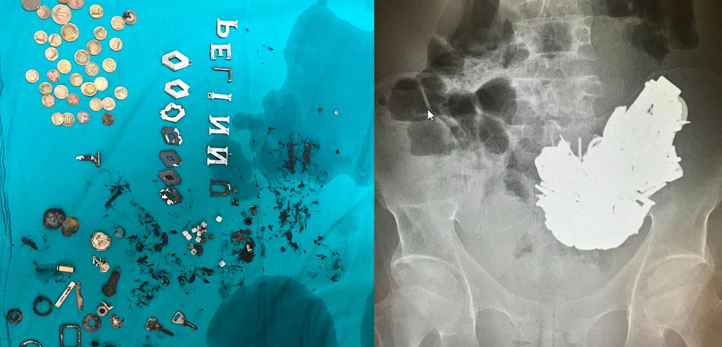

Bornova’da şaşkına çeviren ölüm… 41 yaşındaki E.D. isimli kişi, karın ağrısı şikayetiyle Ege Üniversitesi Tıp Fakültesi Hastanesine gitti. Röntgen çekilerek tedavi alına alınan E.D.’nin midesinde 700 grama yakın farklı 200 metal cisim tespit edildi. Durumu kötüleşen hasta, acil olarak ameliyata alındı. Ameliyatın ardından yoğun bakıma kaldırılan hasta, zehirlenmeden dolayı yaşamını yitirdi.

Ege Üniversitesi Tıp Fakültesi Hastanesi Başhekimi Prof. Dr. Tuncay Göksel, yaptığı açıklamada hastanın psikiyatrik rahatsızlıkları bulunduğuna dikkat çekerek metal cisimleri yuttuğunu ifade etti. Ameliyatın başarılı geçtiğini ve cisimlerin hastanın midesinden çıkarıldığını dile getiren Göksel, zehirlenmeden dolayı hastanın hayatını kaybettiğini belirtti.